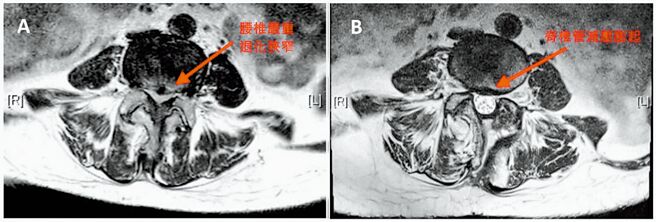

基隆長庚醫院骨科醫師張家偉指出,臨床上每4位脊椎融合手術患者,就有1人有糖尿病,因為葡萄糖是骨骼能量的主要來源,但糖尿病患者胰島素不足,新骨生成能力較差,長期下來容易骨質疏鬆,尤其常出現脊椎狹窄滑脫和椎間盤突出。

張家偉表示,糖尿病患者血糖管控不良,會增加脊椎手術後傷口感染風險,例如可能導致骨髓炎或術後併發症,嚴重甚至會出現菌血症或敗血症,有生命危險。由於傳統脊椎手術通常是開放性進行,並用電燒來移除骨頭上軟組織,出血較多、手術時間較長,周圍組織容易損傷,對糖尿病患者的術後感染控制更困難。

基隆長庚醫院骨科醫師蔡松航說明,超音波骨刀技術是運用超音波振動來切割骨頭,具強力、安全且快速的切割功能,手術過程中出血量大幅減少,能更精準去除病變部位;將此技術結合內視鏡,能使微創手術更高效,手術時間縮短、恢復時間變快,術後感染降至原本的16分之1,特別適合糖尿病患者。